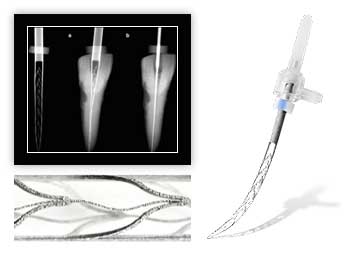

Для этого в стоматологии "Интердентос" есть все необходимые аппараты для диагностики и получения качественных снимков пораженной области. Также, может возникнуть ситуация, когда имеется сильное воспаление, а, пораженный периодонтитом, молочный зуб уже сильно подвижен, в таких случаях показано удаление для предотвращения интоксикации организма ребенка.